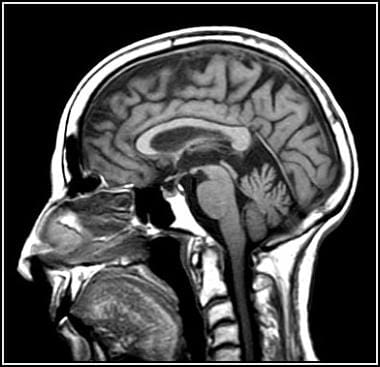

Traumatic brain injuries have different types and levels of severity, according to the Office of the Surgeon General. They can include penetrating injuries, like Giffords’, or mild brain trauma, like the kind often sustained by troops in an explosion. The latter, as we’ve reported, has been called one of the signature wounds of the Iraq and Afghanistan wars, and tens of thousands of cases have been left undiagnosed by the military’s medical system.